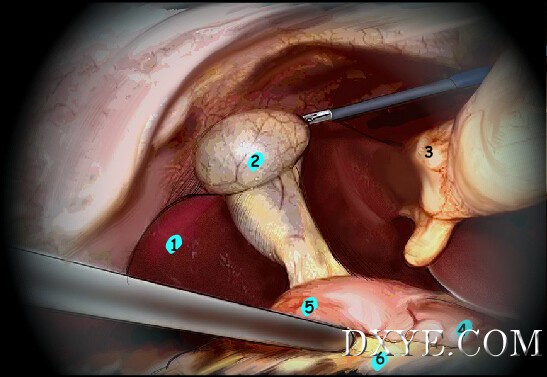

• 解剖结构

1. 肝

2. 胆囊

3. 圆韧带

4. 胃

5. 十二指肠

6. 横结肠

执行对腹腔的快速探查,允许在解剖开始之前识别右上象限的所有解剖结构。